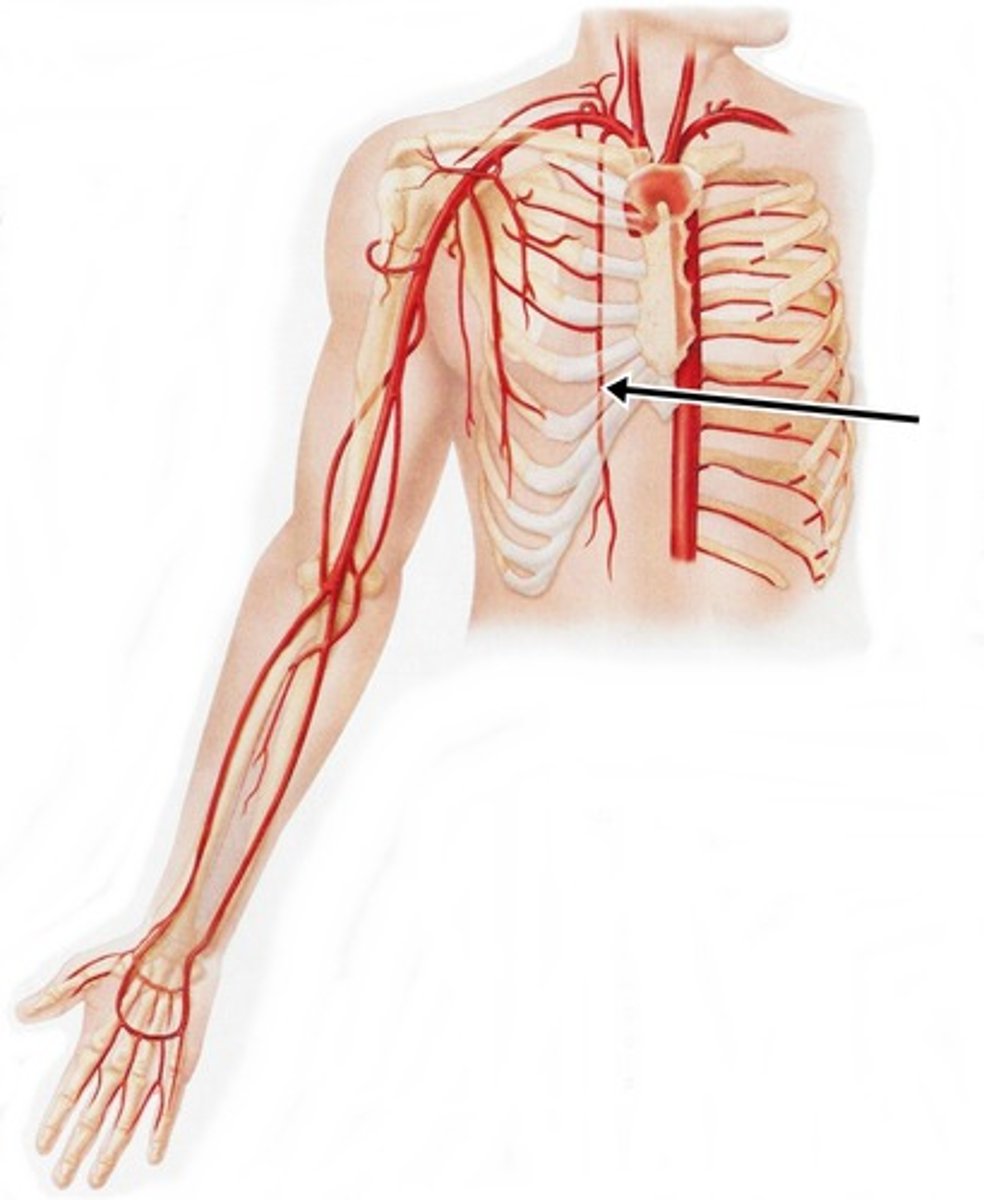

internal thoracic arteries

What is this blood vessel?